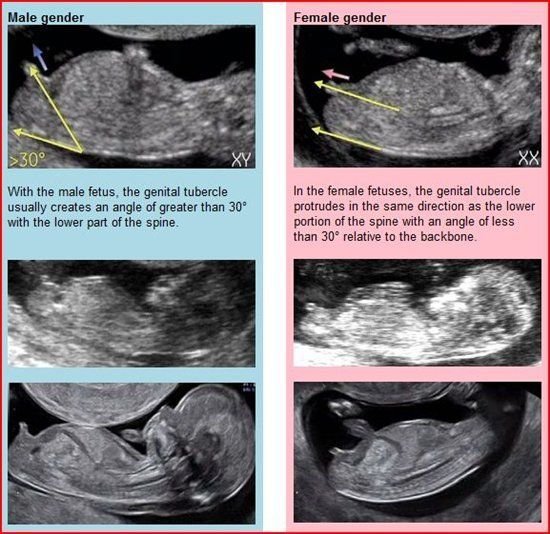

Ето тук е обяснено как се разбира пола толкова рано - т.нар. The nub Theory

На английски е, но с няколко думи се казва, че всички бебета имат генитален туберкул между краченцата в 11-13 седмица и според тази теория ъгъла между тази част и гръбначния стълб при момченцата е по-голям от 30 градуса, при момиченцата - по-малък от 30 градуса. Колкото по-късна седмица, толкова по-голям е процента на сигурност.

@Станислава, ето така, градусите се гледат.